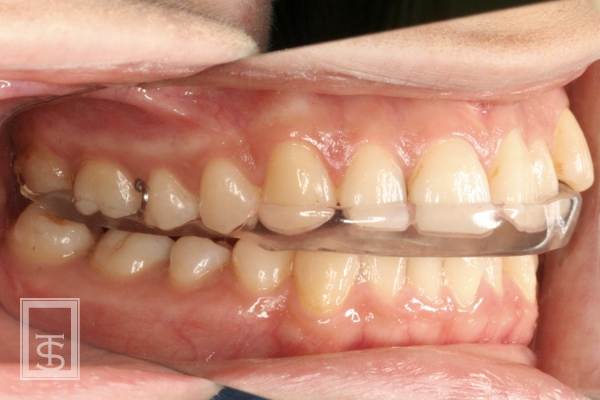

スプリント療法(Splint therapy)

顎関節症治療に用いられている方法で、マウスピース型の装置を口腔内にはめて、顎関節症の原因となっている口腔習癖や左右の顎のアンバランスを改善する治療法となります。

顎関節症状の有る場合、潜在的に顎関節のリスクが高い場合、顎位の不安定な場合などに症状の改善、顎関節のリスク評価、顎位の確認などに行います。

通常は上顎にマウスピース状の装置を使用します。

使用期間は症状や使用状況により異なります。